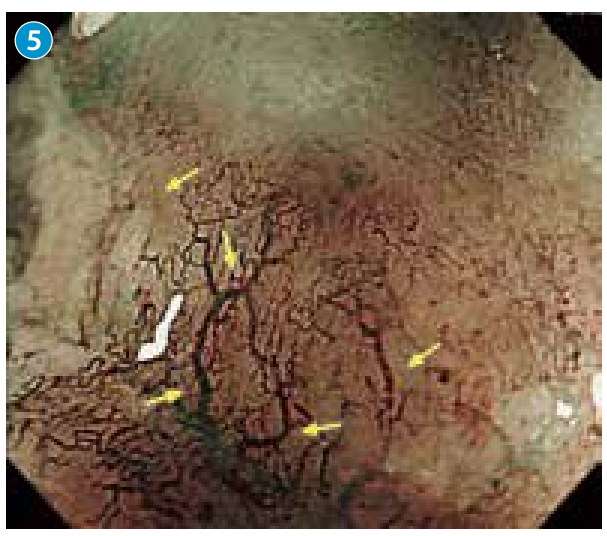

●近距离观察病变顶部凹陷处,见扩张的血管横行、纵行生长,不规则的分支呈网状分布。

●NBI下弱放大观察,顶部呈现较浅但依然可以识别的褐色区域(brownish area),内部为树枝状分布、不规则、缺乏环状的异常血管。

●观察到缺乏环状、不规则、树枝状的血管网。判断为不规则的R型血管(→)

。